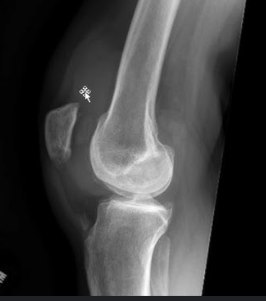

영상검사: 엑스레이, 초음파, MRI 등으로 관절 상태 확인